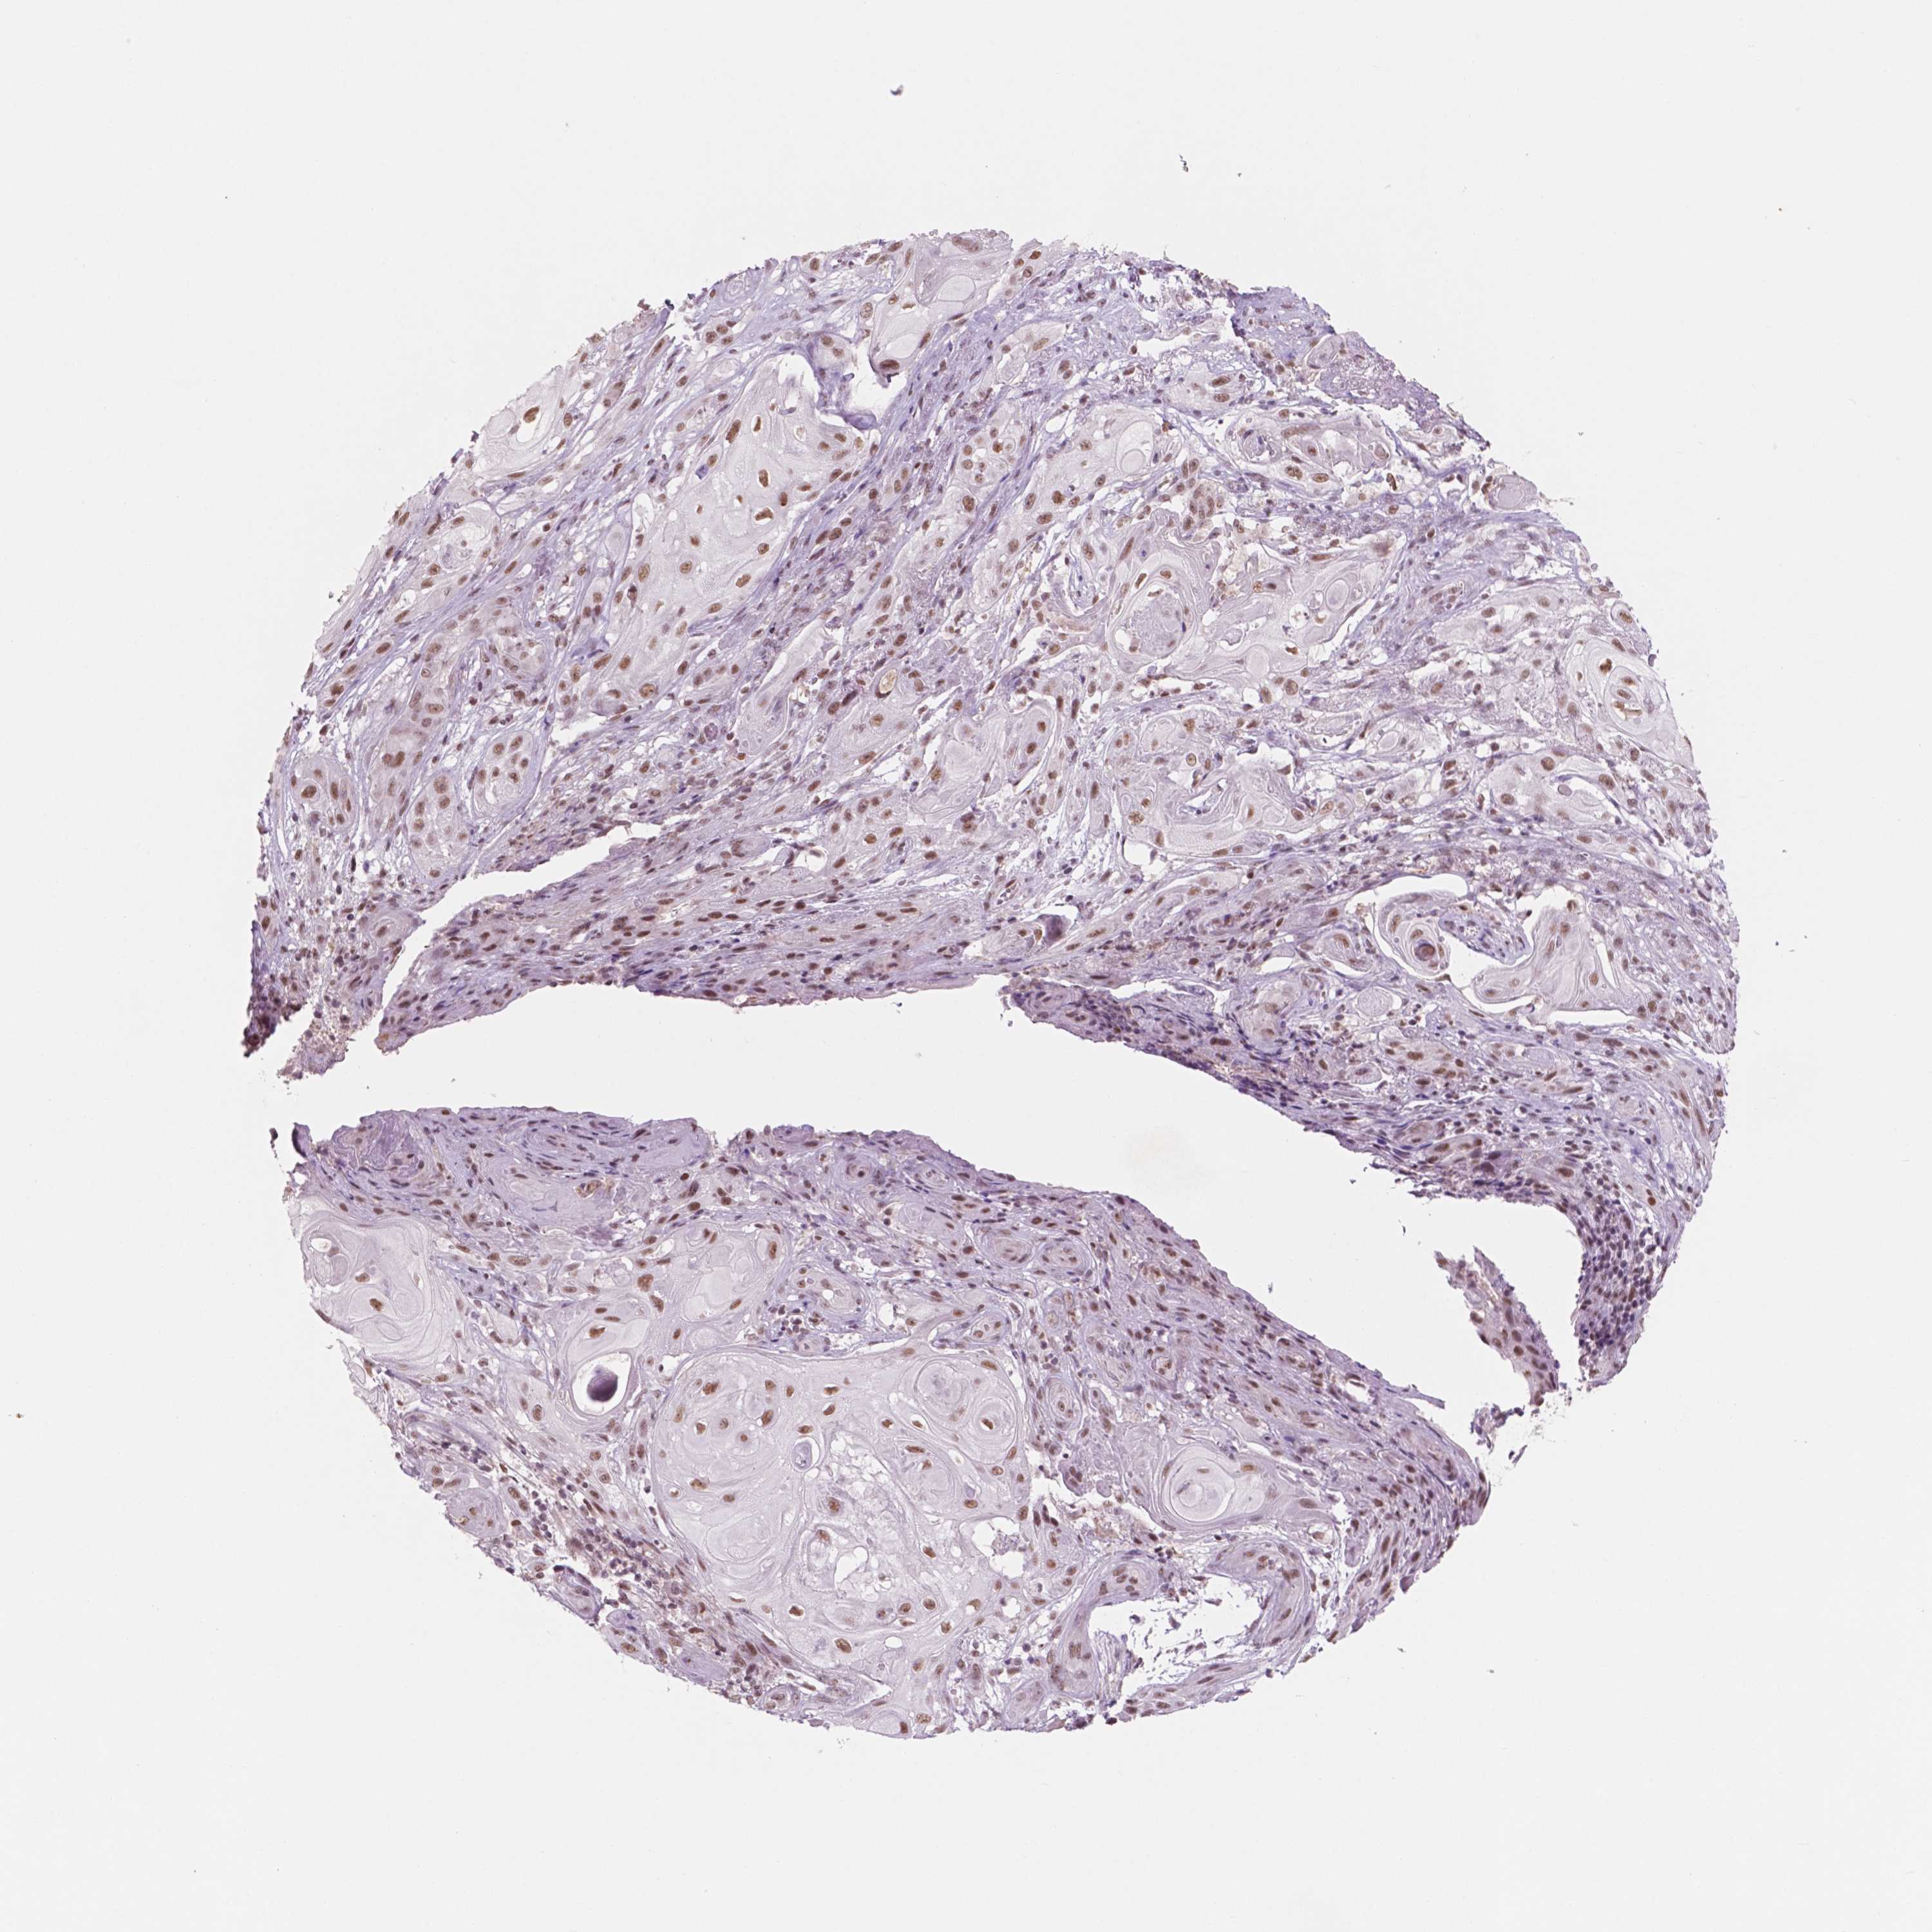

SKIN CANCER - Protein expressioni

A mouse-over function shows sample information and annotation data. Click on an image to view it in a full screen mode. Samples can be filtered based on level of antibody staining by selecting one or several of the following categories: high, medium, low and not detected. The assay and annotation is described here.

Antibody staining in the annotated cell types in the current human tissue is reported as not detected, low, medium, or high, based on conventional immunohistochemistry profiling in selected tissues. This score is based on the combination of the staining intensity and fraction of stained cells.

Each image is clickable and will lead to virtual microscopy that enables deeper exploration of all samples and also displays staining intensity scores, fraction scores and subcellular localization as well as patient and tissue information for each sample.

Antibody HPA068122

Staining

High

Intensity

Strong

Quantity

>75%

Location

Nuclear

Basal cell carcinoma

Squamous cell carcinoma, NOS